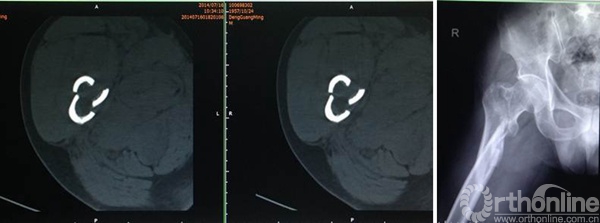

邓XX,男,56岁

术后8周